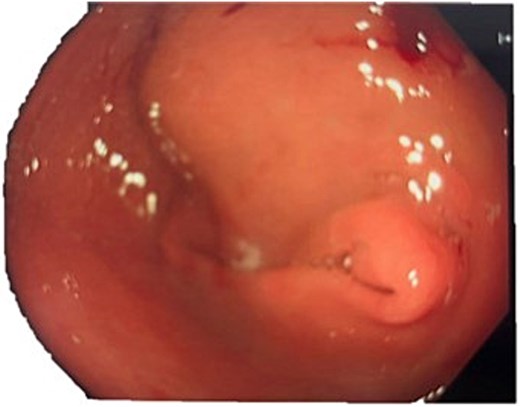

A computed tomography (CT) of the abdomen with IV portal venous contrast demonstrated proximal gastric dilatation due to a 7.6 cm gastric pyloric mass concerning for malignancy (Fig. 1). Other findings included small volume pancreatic parenchymal calcifications with no ductal dilatation. She was decompressed via nasogastric tube and planned for gastroscopy and feeding tube insertion. Gastroscopy demonstrated a partially obstructing extraluminal mass at the gastric antrum, able to be traversed to the second part of the duodenum (Fig. 2). A nasojejunal feeding tube was placed and the nasogastric tube was left in for decompression. An endoscopic ultrasound the following day demonstrated Doppler signal in the mass, confirmed to be a large 6.2 × 4.2 × 7.0 cm pseudoaneurysm arising from the GDA on a subsequent CT mesenteric angiogram (Fig. 3). Coil angioembolization of the pseudoaneurysm was successfully done via common femoral access (Fig. 4). She was commenced on NJ feeding and supplemental parenteral nutrition. She recovered well and was discharged on puree diet. Repeat imaging at 4 weeks demonstrated resolution of the pseudoaneurysm and returned to normal diet 6 weeks post presentation.

Contrast-enhanced CT of the abdomen. Axial view showing gastric outlet obstruction.